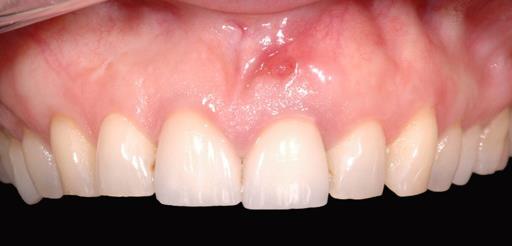

1/18 - Longitudinal fracture on the root resected tooth 21 with visible buccal fistulaGBR together with soft tissue augmentation with mucoderm® and maxresorb® - Dr. S. Scherg